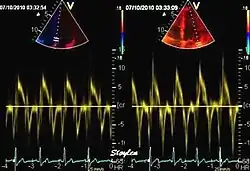

Spectral tissue velocity curves from the mitral annulus at the septal (left) and lateral (right) points. The curves show multiple heartbeats.

Pulsed wave spectral tissue Doppler has become a universal tool that is part of the general echocardiographic examination. Like any other echocardiographic measurement, measures by tissue Doppler should be interpreted in the context of the whole examination. The velocity curves are in general taken from the base of the mitral annulus at the insertion of the mitral leaflets, in the septal and lateral points of the four chamber view, and eventually the anterior and inferior points of the two-chamber views. For the right ventricle it is customary to use the lateral point of the tricuspid annulus only. Averaging peak velocities from the septal and lateral point has become common, although it has been shown that averaging all four points mentioned above, gives significantly less variability[3]

The method measures annular velocities to and from the probe during the heart cycle.

Single spectral tissue velocity curve from the mitral annulus. The curve shows velocities towards the probe (positive velocity) in systole, and away from the probe (negative velocities) in diastole. The most useful measures are the peak velocities, in systole S' and in early diastole (e') and late diastole during atrial contraction (a').

Annular velocities summarize the longitudinal contraction of the ventricle during systole, and elongation during diastole. Peak velocities are commonly used.